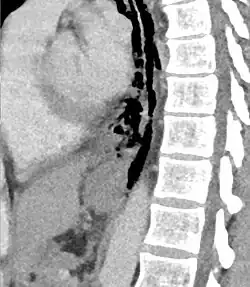

Hours to days later, pleural effusion(s) with or without pneumothorax, widened mediastinum, and subcutaneous emphysema is typically seen. CT scan may show esophageal wall edema and thickening, extraesophageal air, periesophageal fluid with or without gas bubbles, mediastinal widening, and air and fluid in the pleural spaces, retroperitoneum or lesser sac.